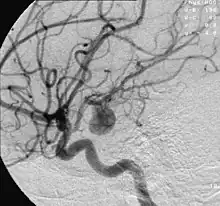

La neuroradiologie interventionnelle est la partie de la radiologie interventionnelle spécialisée dans le traitement (coïls[Note 1], stents) des malformations vasculaires du cerveau et de la moelle épinière (par exemple, anévrismes intracrâniens) qu'elles soient congénitales (angiomes) ou acquises (accidents ischémiques cérébraux, fistules durales et méningées).

C'est également l'une des meilleurs manières de traiter un anévrisme, une malformation artério-veineuse cérébrale ou un accident vasculaire cérébral (AVC) ischémique[1]. Le développement de cette spécialité en France, qui permet de lutter contre les conséquences des AVC en multplication, est liée à la collaboration entre chercheurs, ingénieurs (BALT[2]) et médecins.

Elle utilise les techniques de la radiologie dont la tomodensitométrie, l'imagerie par résonance magnétique (IRM) ainsi que les examens vasculaires cérébraux (angiographie).